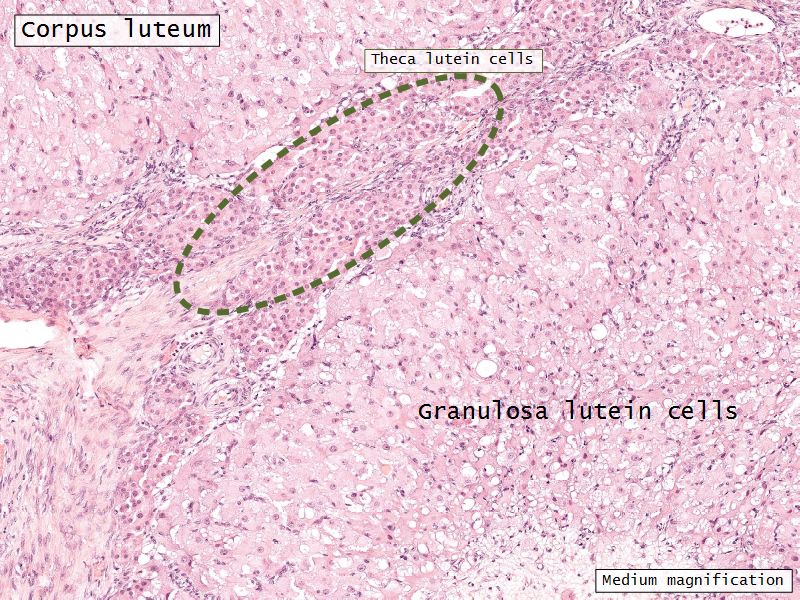

- Two major cell types

- Granulosa lutein cells

- modified granulosa cells

- Theca lutein cells

- modified theca interna cells

- Many capillaries

Granulosa lutein cells

- Modified granulosa cells

- Large - 30µm

- Pale cells

Theca lutein cells

- Modified theca interna cells

- Smaller - 15µm

- Dark stained